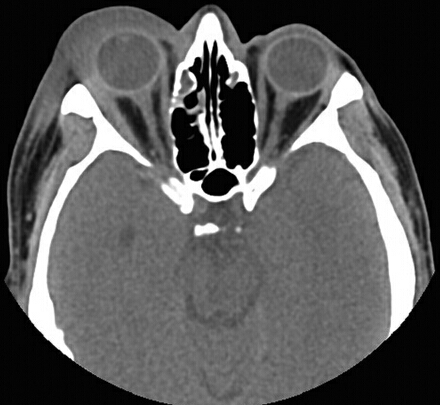

复视